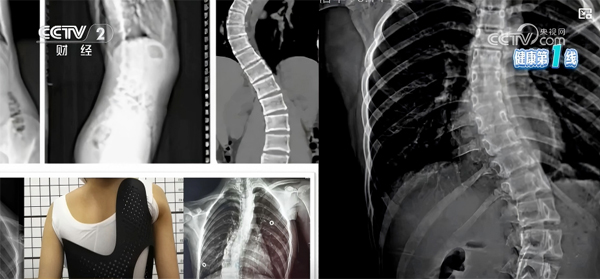

脊柱侧凸是一种复杂的脊柱三维畸形,国际脊柱侧凸研究学会(SRS)明确将其定义为:在站立位全脊柱冠状面X线片测量Cobb角≥10°。其中,特发性脊柱侧凸病因尚不明确,约占脊柱侧凸

脊柱侧凸是一种复杂的脊柱三维畸形,国际脊柱侧凸研究学会(SRS)明确将其定义为:在站立位全脊柱冠状面X线片测量Cobb角≥10°。其中,特发性脊柱侧凸病因尚不明确,约占脊柱侧凸发病率的80%,而青少年特发性脊柱侧凸(AIS)是最常见的类型,发生于10~18岁青少年群体。

矫形支具是国际公认的控制脊柱侧弯进展最有效的非手术手段之一,适用于Cobb角超过20°且进行性加重风险较大的中重度脊柱侧弯患者,可单独应用,若同时配合专项康复训练,矫正效果会更佳。根据材质、矫正原理的不同,临床常用支具分为硬支具和软支具两类。

软支具为新型弹性支具,基于动态三维三点力生物力学原理,通过柔和精准的推压力启动神经肌肉调控,引导身体主动保持正确姿态,舒适度更高,适用于轻度侧弯或作为中度侧弯的辅助矫正。

支具治疗对患者依从性要求较高,硬支具通常需每天佩戴16-23小时,软支具通常需每天佩戴8-11个小时,定期复查并调整支具规格,才能确保矫正效果。